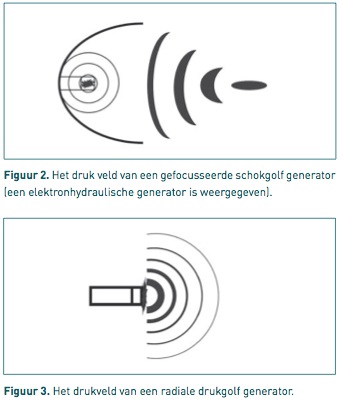

1) Focused

Focused ESWT systems producing focused shock waves, deposit the energy

on one point or focus. Thus the energy per mm³ is much bigger compared to the

radial system. The depth of the focus can be chosen. This type of shock wave

system is also used in human medicine for the crushing of kidney stones.

There are three different types for generating focused shockwaves:

-

Electro-hydraulic (EH)

- Electro-magnetic (EM)

- Piëzo-electric (PE)

2) Radial

Radial Shock waves produced by a pneumatic hammer are emitted in a

radial way. Thus the intensity of the shock waves is the highest at the surface

(the skin) and gets lower and lower when moving further away from the hammer.

The waves are diverging.

This type of ESWT can be used for the treatment of

superficial structures. Treatment of deeper structures is more difficult because

the diverging shock waves lose lots of energy before getting at the place to be.